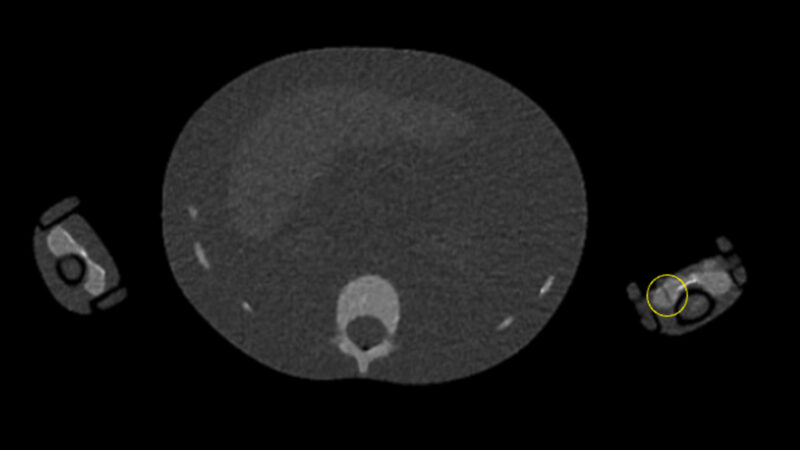

Des chercheurs suisses ont établi une revue de la littérature sur l'extravasation des produits de contraste au scanner. Plusieurs travaux ont évalué des stratégies de limitation des risques, en amont et pendant l'injection. L'article est en libre accès.